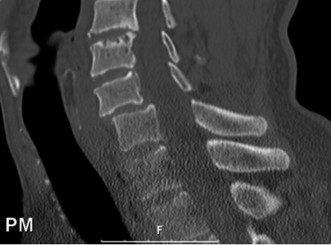

CASE 1 A 63-year-old male sustained a hyperextension injury to his neck while diving into a pool. Upon presentation, he reports decreased sensation in his hands and decreased strength in his arms and wrists, but no lower extremity complaints. On motor examination, he has 5/5 strength in his deltoids and elbow flexors and 4/5 strength in the elbow extensors, wrist extensors, and finger flexors. Lower extremity motor examination is normal. Sensation is decreased to light touch in both hands. Otherwise his sensation is preserved. Images of his cervical spine are shown in Figures 1–1 to 1–3.

Figure 1–1

The correct answer is (B). The clinical scenario describes a patient with central cord syndrome (CCS). CCS continues to be the most common incomplete spinal cord injury accounting for 15.7% to 25% of all spinal cord injuries. The characteristic presentation is an extension moment injury in a previously spondylotic and stenotic spine. Figures 1–1 to 1–3 demonstrate a spondylotic spine with central narrowing and CSF effacement that is worst at the C3–4 level. Bleeding, edema, and/or Wallerian degeneration lead to damage of the lateral corticospinal tract which is the main descending motor tract in the spinal cord. The more central anatomic position of the homunculus to the upper extremities places them at greater risk than those to the lower extremities. As such, injury to the lateral corticospinal tract is characterized by upper more than lower extremity involvement and motor deficits being more pronounced than sensory deficits.